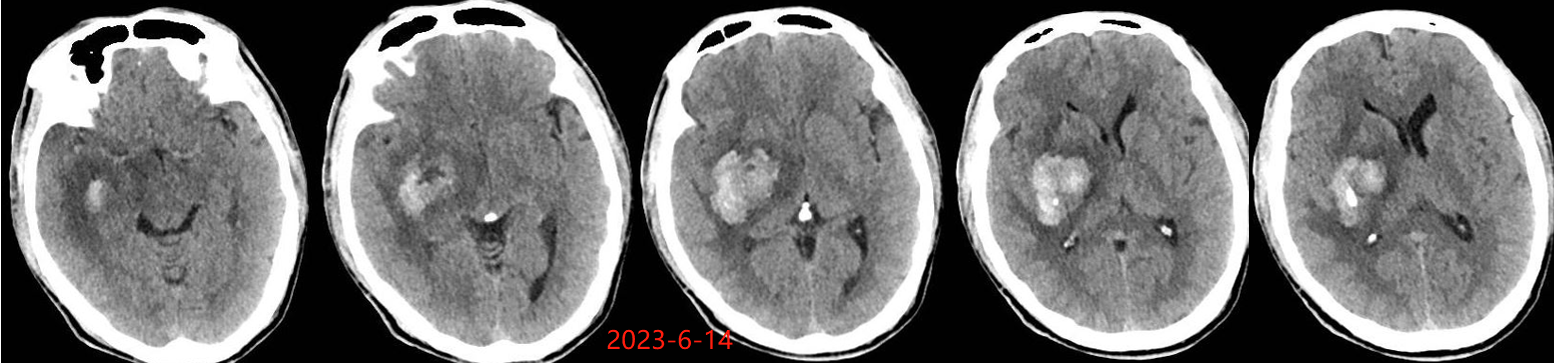

入院后于当地医院完善头颈部CTA检查未见明显血管发育异常,于2023-6-7行血肿钻孔引流术+脑室内颅内压监护探极置入术,引流一周后拔除引流管,期间未行尿激酶注射,患者反应情况逐渐好转,肌力未见明显改善。于出血后3周左右脑水肿基本消退后出院行康复治疗,治疗过程中患者肌力曾有所改善,左侧肢体肌力最好可达3级。术后3月左右患者一般状态逐渐变差,无发热,神志逐渐进展为昏睡状态,左侧肢体肌力1级,复查颅脑CT示水肿较前明显加重,颅脑MRI示右侧基底节区长T1长T2团块状病变,内有囊变,呈不均匀菜花样强化,考虑为高级别胶质瘤可能性大。遂行开颅病灶大部切除+去骨瓣减压术,术后病理提示高级别胶质瘤伴囊变,后续行同步放化疗STUPP方案,PTV:60Gy/30F/6周,替莫唑胺350mg化疗。患者右侧基底节区病灶相对稳定,2024-9-3复查颅脑MRI可见脑室内新发病灶。患者目前KPS 60分,神志清醒,精神差,反应迟钝,语言对答部分切题,右侧肢体自主活动,左侧肢体肌力2级。

胶质瘤出血灶周围水肿一般较广泛,同血肿期龄存在明显不符的征象,出血后早期即有明显水肿,此时并非血肿引起,而是肿瘤机械压迫、脑皮质受损,肿瘤细胞的分泌作用及细胞毒性等多因素共同作用所致,且水肿持续时间长。 高血压性脑出血的水肿一般在出血后 3 h 出现,48 h 达高峰,4 d 后开始逐渐消退,2-3 周后基本消失。该患者脑水肿出现的时间相对较早、重,且持续时间长,有别于一般的高血压脑出血。若该患者若第一次出血行钻孔引流时,术中能留取标本查到肿瘤脱落细胞,则会使该患者的诊断提前;当然对于该患者也不能完全排除单纯脑出血后,周围脑组织水肿缺氧等微环境的改变诱发胶质瘤的发生。总之,对于既往无脑出血高危因素且脑血管检查未见明显异常的脑出血患者,若脑水肿出现早且持续时间长,应警惕肿瘤卒中可能。